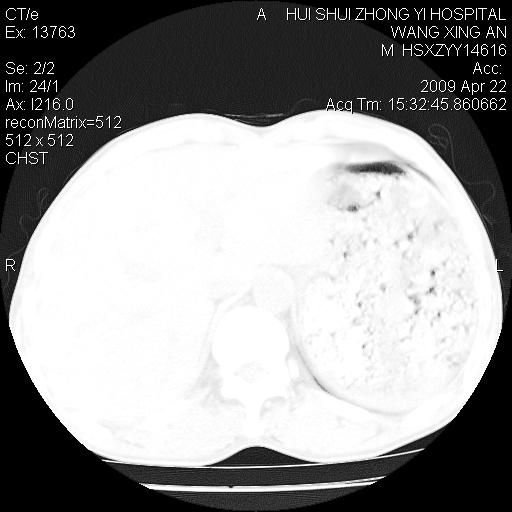

标题: CT19534:患者男、46岁咳嗽、胸痛半月。 [打印本页]

标题: CT19534:患者男、46岁咳嗽、胸痛半月。

考虑---右肺中心型肺癌继发下叶不张,少量胸水。

支持右侧中央型肺ca并右下肺不张、右侧胸腔少量积液。

1、右下肺中央型肺癌并右肺转移,右肺下叶不张。(右肺有结节影)。

2、右中上肺陈旧性肺结核(因为大多为纤维灶)。

3、右侧胸腔积液。

1、右下肺中央型肺癌并右肺转移,右肺下叶不张。(肿块围绕右肺下叶支气管生长,致管腔闭塞右肺下叶不张;右肺有结节影)。

2、右侧胸腔积液。

3、右中上肺陈旧性肺结核(右肺见纤维化病灶及点状钙化)。

1、右下肺中央型肺癌并右肺转移,右肺中下叶不张。(右肺有结节影)。胸骨转移

1)右肺中间段支气管癌并右肺下叶肺不张。2)右肺上叶、两肺下叶背段感染性病变。3)右侧少量胸腔积液。